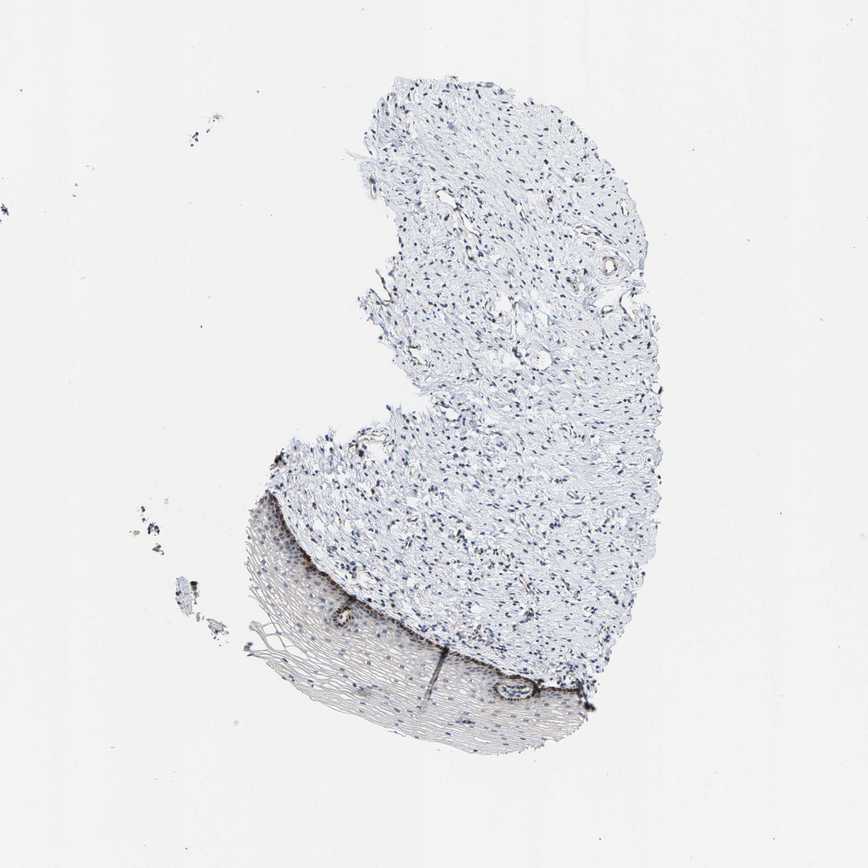

CERVIX - Antibody stainingi

Antibody staining in the annotated cell types in the current human tissue is reported as not detected, low, medium, or high, based on conventional immunohistochemistry profiling in selected tissues. This score is based on the combination of the staining intensity and fraction of stained cells.

Each image is clickable and will lead to virtual microscopy that enables deeper exploration of all samples and also displays staining intensity scores, fraction scores and subcellular localization as well as patient and tissue information for each sample.

Antibody HPA016419Antibody HPA019625

Glandular cells LowLow

Squamous epithelial cells LowMedium